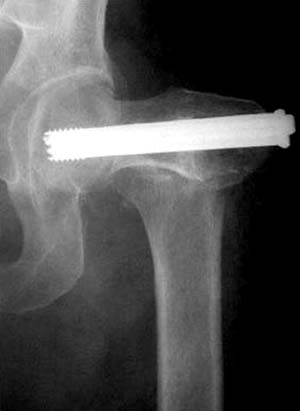

Правильная техника фиксации - это три параллельных  каннюлированных винта под углом 130 -135 градусов к диафизу, не ниже уровня малого вертеля. Проведенные ниже вертела винты с бОльшим углом (более вертикальные) в 20% осложнялись подвертельными переломами бедра. Ближе к кортикальному слою винты с длинным контактом резбовой части, а также каннюлирванные механически лучше, чем сплошные. Расположение винтово - в  в виде V т.е. один внизу по калькару и два сверху-спереди и сзади.

Имя     : 1 Fem neck intraop ap.jpg

Тип     : image/jpg

Размер  : 26253 байтов

Описание: отсутствует

Url     : http://weborto.net:8080/pipermail/ortho/attachments/20120118/c4b77b39/attachment-0005.jpg